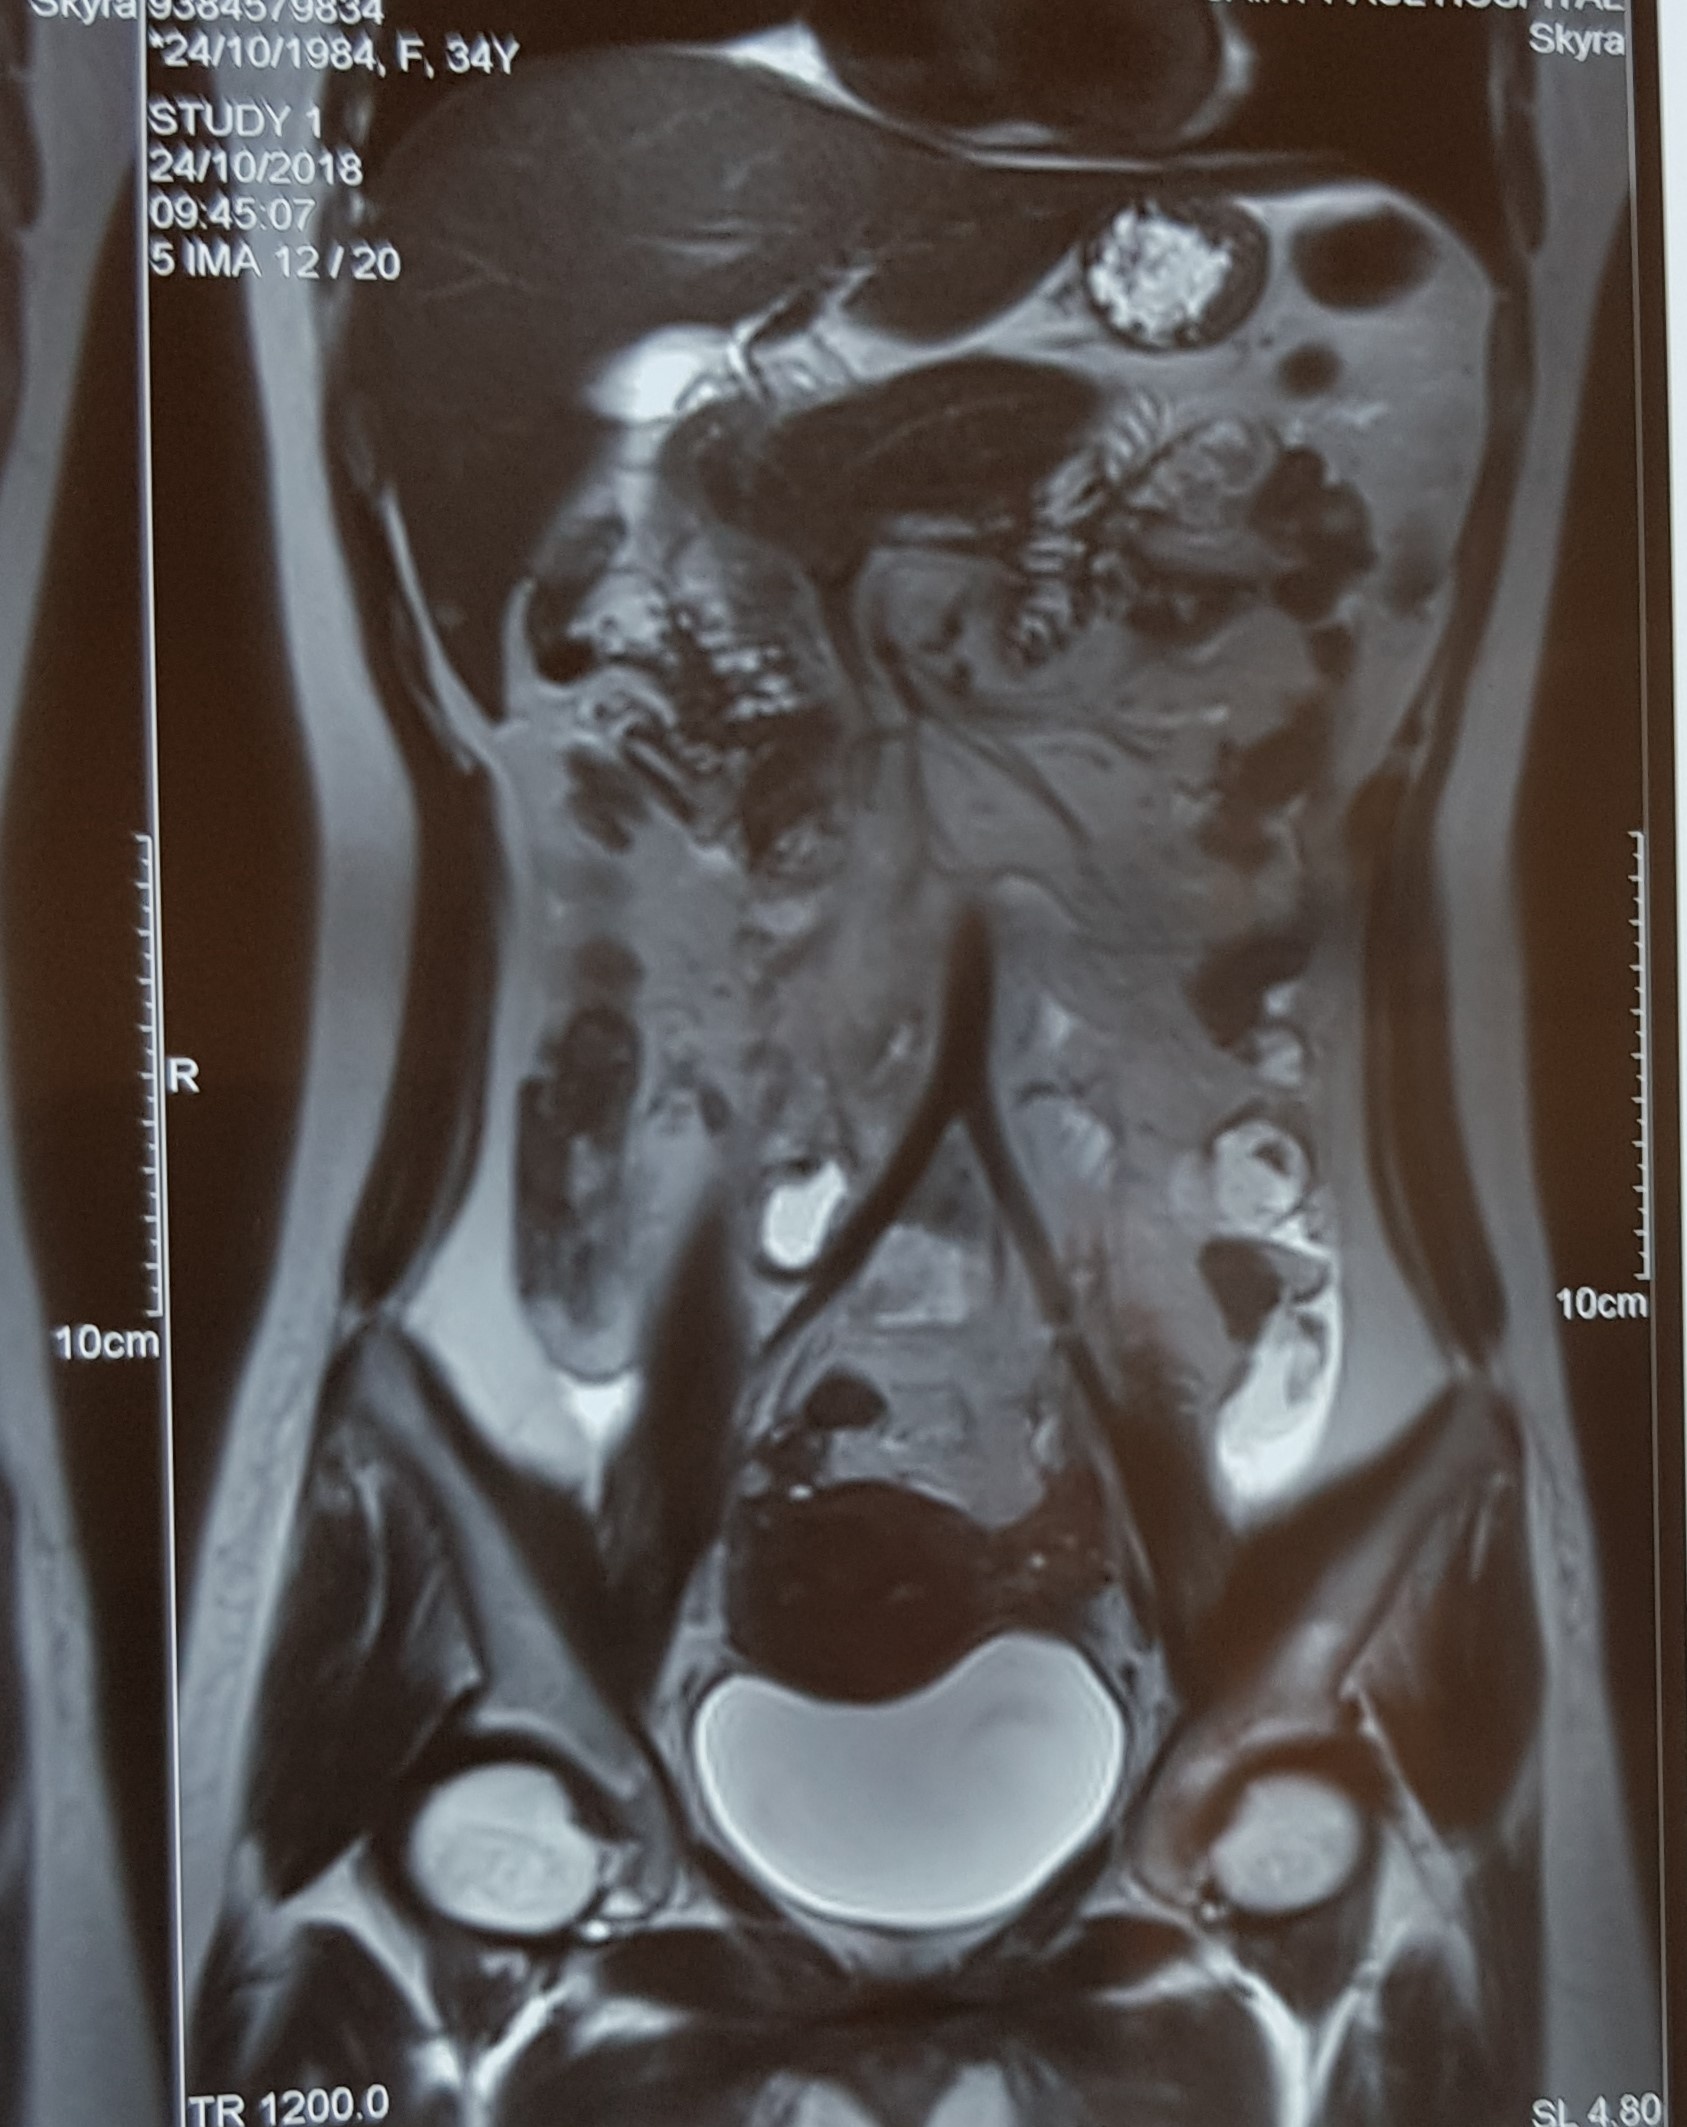

Bệnh nhân Trần Thị Quỳnh (đã đổi tên, sinh năm 1984 ở Xuân Tảo, Bắc Từ Liêm, Hà Nội) đến Bệnh viện Phụ Sản Hà Nội thăm khám vì thấy có hiện tượng ra máu âm đạo sau 30 ngày chuyển phôi. Các bác sĩ khoa D5 của bệnh viện chẩn đoán hình ảnh siêu âm không có túi thai trong buồng tử cung, nghi ngờ mang thai ổ bụng. Chỉ số beta HCG của sản phụ là 19.000-29.000 mIU/ml càng tăng thêm nghi ngờ của bác sĩ. Hình ảnh siêu âm và chụp MRI cho thấy vùng hố chậu phải cạnh động mạch chậu cách chỗ chia nhánh 35 mm có túi thai kích thước 25x20 mm bên trong có túi noãn hoàn.